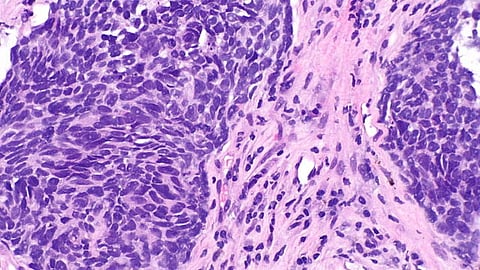

The study examined the effect of steroids on a type of immunotherapy known as immune checkpoint inhibitors (ICIs). ICIs help the body's immune system fight cancer by blocking proteins that prevent T-cells from attacking cancer cells. ICIs are often used to treat non-small cell lung cancer, the most common form of lung cancer.

They also determined that the T-cells of significant numbers of patients on steroids were not fully matured and launched a preclinical study using mice to observe the effects of steroids on ICI therapy in real time. This mouse model study led to the discovery that steroids given before/during immunotherapy inhibit T-cells from fully maturing.